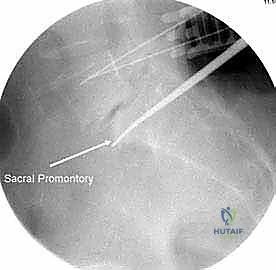

* الأشعة السينية (X-rays): خاصة الصور الديناميكية (أثناء الانحناء للأمام والخلف) لتقييم درجة عدم الاستقرار الميكانيكي والانزلاق.

* التصوير المقطعي المحوسب (CT Scan): يوفر صوراً ثلاثية الأبعاد للعظام، وهو ضروري جداً للتخطيط الجراحي الدقيق وتحديد أحجام المسامير المناسبة لكل سويقة فقارية.